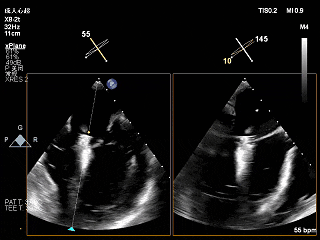

术前Bicom切面

术前X-Plane

术前瓣口面积5.39cm²

后叶长度9.24cm

可用房间隔穿刺高度4.03cm

3D-ZOOM 彩色多普勒显示反流主要来源于2区